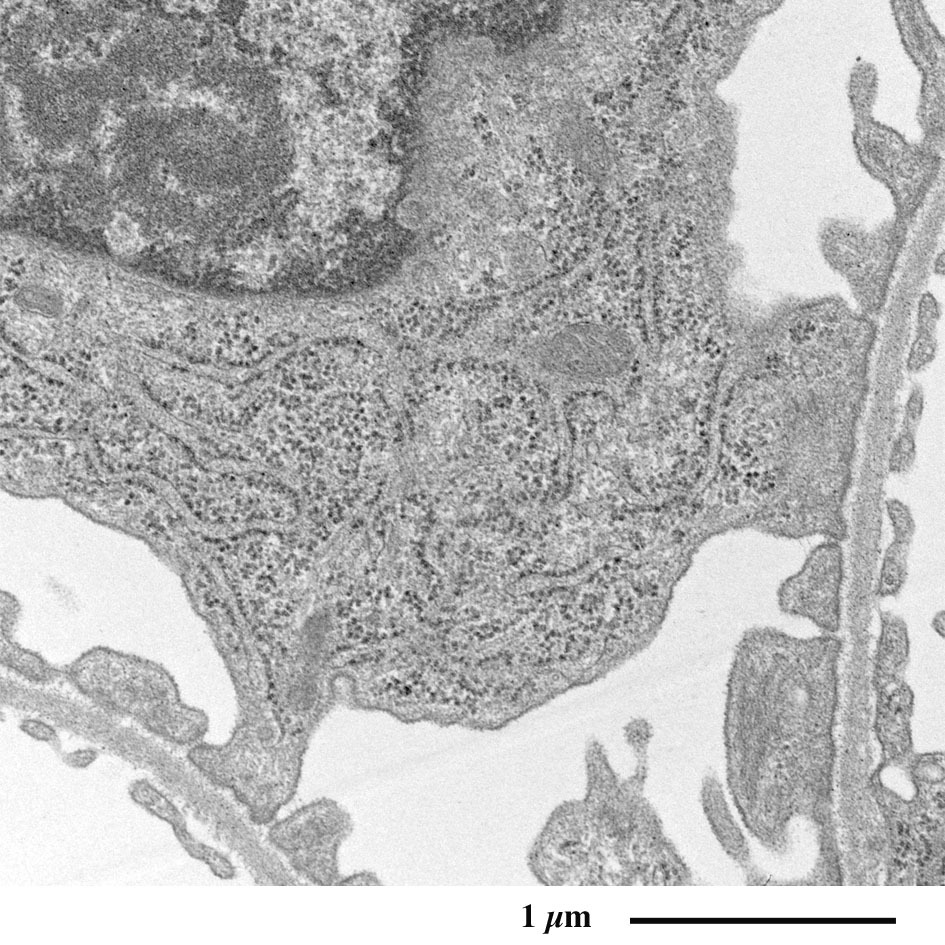

【 超薄切片の透過型電子顕微鏡画像 】

Transmission electron microscopic image of ultrathin section

足細胞の発達したゴルジ装置(赤)

足細胞の発達した粗面小胞体